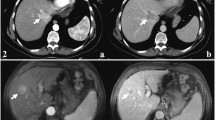

T1- and T2-weighted signal intensity (SI), restricted diffusion, transitional phase (TP) and hepatobiliary phase (HP) aspects allowed the differentiation between study group (mass-forming ICCs) and each other control group (A, C, D, E) with statistical significance, while arterial phase (AP) appearance allowed the differentiation between study group and the control groups C and D with statistical significance and PP appearance allowed the differentiation between study group and the control groups A, C and D with statistical significance. Instead, no MR feature allowed the differentiation between study group (periductal-infiltrating type) and control group B.

T1 and T2 W SI, restricted diffusion, TP and HP appearance allowed the differentiation between mass-forming ICCs and mimickers with statistical significance, while AP appearance allowed the differentiation between study group and the control groups C and D with statistical significance and PP appearance allowed the differentiation between study group and the control groups A, C and D.